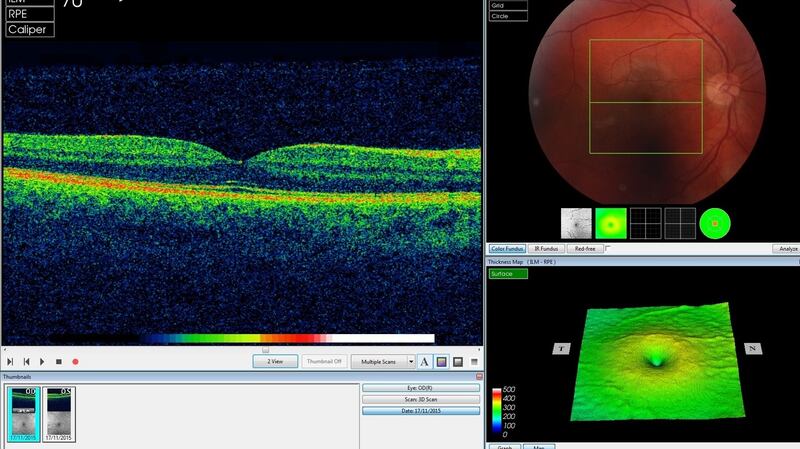

OCT is similar to ultrasound but uses light rather than sound waves to generate 3D digital images, which provide a detailed map of the eye, but are hard to read and need expert analysis to interpret, Keane explains. If people suddenly develop a problem, such as a bleed at the back of the eye, delays could cost patients their sight but already the AI tool is reducing incidence of AMD.

The first neural network (the segmentation network) analyses the OCT scan to provide a map of the different types of eye tissue and the features of disease it sees. This map allows eyecare professionals to gain insight into the system’s “thinking”.

The second (the classification network) analyses this map to present clinicians with diagnoses and a referral recommendation. Crucially, the network expresses this recommendation as a percentage, allowing clinicians to assess the system’s confidence in its analysis.